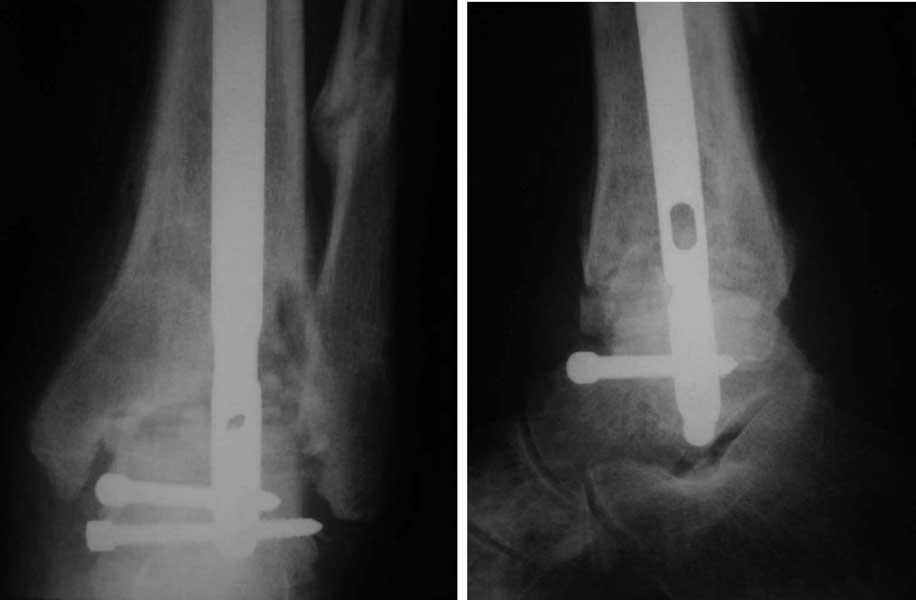

Интересный случай. Допускаю, что состояние мягких тканей приемлемое. Цель лечения должна заключаться, как мне кажется, в ликвидации ложного сустава и достижении артродеза голеностопного сустава. Впрочем, это две взаимосвязанные задачи. Мы бы оперировали следующим образом. Остеотомия малоберцовой кости на вершине деформации. Передне-медиальным доступом артротомия голеностопного сустава, резекция суставных поверхностей с отломков большеберцовой и таранной костей, удаление рубцов между отломками дистального эпиметафиза большеберцовой кости, антеградный стержень с дистальным блокированием в таранной кости, костная пластика дефекта спонгиозным костным трансплантатом из крыла (возможно сразу из двух) подвздошной кости. Банальные артродезы голеностопного сустава мы обычно выполняем антеградным блокированным стержнем (см. вложенный файл),

что позволяет сохранить подтаранный сустав, и нагружать ногу сразу после операции.

Артродез штифтом

С моей точки зрения, которая базируется на личном опыте, артродез голеностопного сустава блокированным стержнем крайне эффективная процедура, как и банальный интерлокинг переломов. При условии, что он выполнен по показаниям, технически грамотно и точно. Тогда начинает действовать принцип – «забил и забыл». Много нюансов. Начиная от количества, направления и расстояние между блокирующими отверстиями на дистальном конце стержня и кончая, например, типом дрели, которой вы пользуетесь в операционной. Но, наверное, прав был Джолдас, когда писал, что необходимо учитывать опыт хирургов. Мне кажется, что вам не стоит осваивать этот метод на таком непростом случае, а воспользоваться методикой, которой вы хорошо владеете. Методика интерлокинга, которой пользуемся мы, отличается от стандартных рекомендаций. Весь интерлокинг на голени мы выполняем с помощью спицевого дистракционного аппарата «custom-made» (фото уже были на форуме), который позволяет устранить все виды смещений большеберцовой кости, расположить суставную поверхность таранной кости перпендикулярно длинной оси проксимального отломка, привести в соосность центр костномозгового канала проксимального отломка большеберцовой кости и центр таранной кости до введения стержня, и удерживать их в таком положении на протяжении всей операции. Остальное дело техники при наличии соответствующего стержня и инструментов.